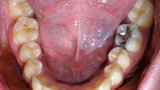

ClearCorrect treatment of crowding